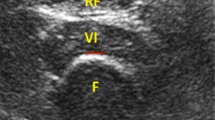

Due to their importance in performing a wide range of physical activities in everyday life, the thigh muscles were the focus of study (Hurley et al. 1998; Moxley Scarborough et al. 1999). All measurements were obtained using a 3 T MRI system (MAGNETOM Verio, Siemens AG). Participants lay supine with the midpoint of the right femur positioned at magnet isocentre and marked with a cod liver oil capsule. Mechanical excitation was introduced to the muscle via a plastic ring positioned 2 cm below the mid-femur point and which was connected to the vibration source via a carbon fibre piston. The ring was firmly secured to the leg using Velcro strapping to ensure good wave transmission (Fig. 1).

Localiser scans were performed prior to MRE to identify the position of the mid-femur landmark. MRE data were acquired using a modified single-shot EPI sequence, sensitized to motion perpendicular to the image plane. Imaging parameters were TR = 1600 ms, TE = 56 ms, FOV = 235 mm, matrix = 128 × 128, slice thickness = 10 mm, scan duration = 40 s, 8 phase offsets acquired capturing the wave propagation (Fig. 2). The external vibration frequency was 50 Hz, with a matching 50 Hz motion-encoding gradient. A three-point Dixon sequence (T1-weighted spoiled gradient recalled (SPGR)) with echo times of 2.46 ms and 8.61 ms (corresponding to the OP and IP times of water and fat MR signals) was used to calculate fat fraction and for muscle CSA measurement. Images were also acquired with an additional OP echo (TE = 4.92 ms) to enable calculation of a T2* correction value. Other parameters were TR = 213 ms, FA = 70̊, FOV = 460 mm, acquisition matrix 256 × 256, and slice thickness = 8 mm.